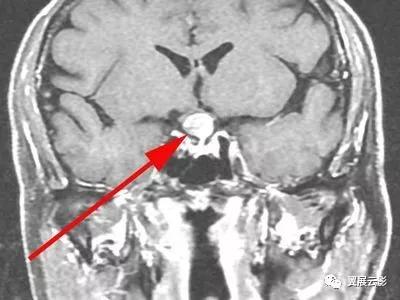

病例2:鞍结节脑膜瘤

鞍结节脑膜瘤重点强调肿瘤的基底部附着于鞍结节,肿瘤的信号,形态,增强扫描所见及蝶鞍大小,形态有无变化,邻近结构受压情况等。诊断时应注意与垂体瘤,颅咽管瘤及鞍隔脑膜瘤等相鉴别。